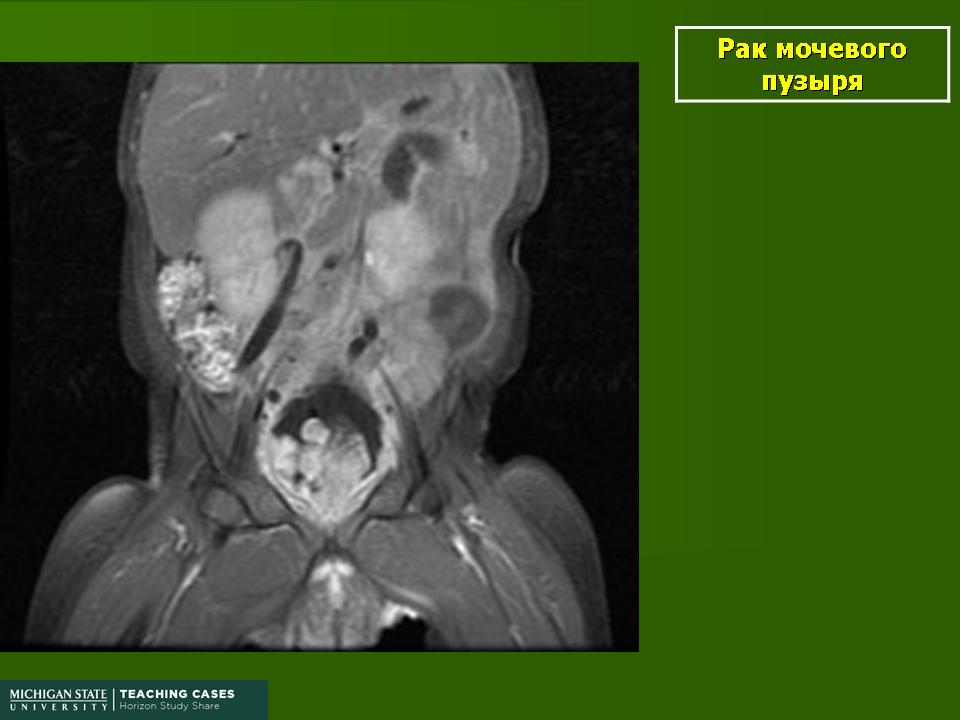

Рак мочевого пузыря.

Приложения:

1.rak_.slayd85.jpg2.rak_.slayd86.jpg